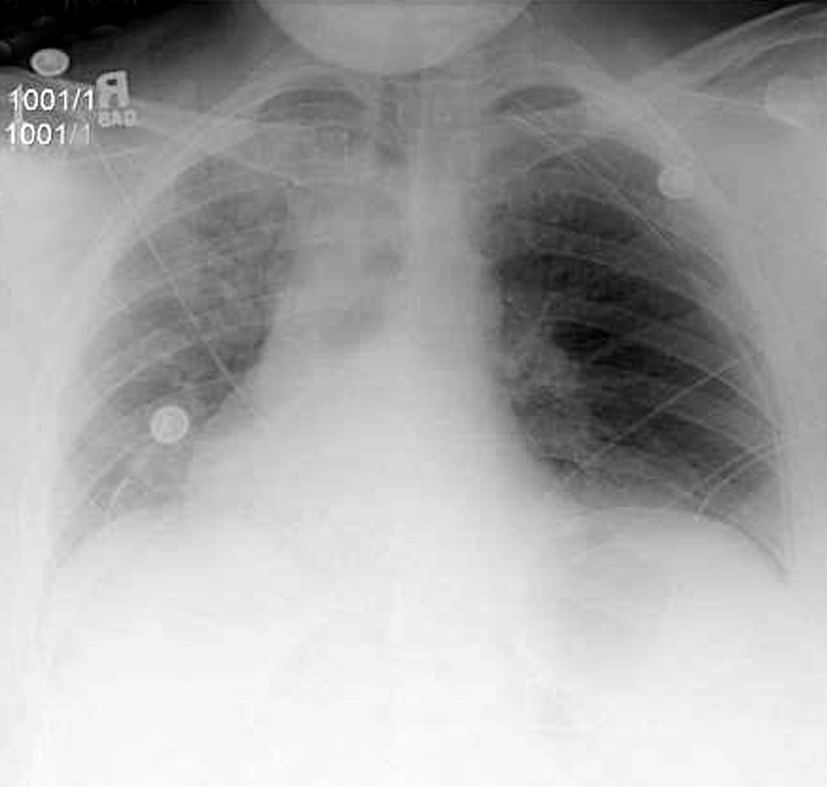

Chronic appearing pleural and parenchymal changes are seen bilaterally with partial eventration of the right hemidiaphragm. Diaphragmatic contour is eccentric with upward bulging of affected portion of diaphragm Usually anteromedial aspect of right hemidiaphragm Paralysis. Diaphragmatic eventration refers to an abnormal contour of the diaphragmatic dome with no disruption to the diaphragmatic continuity.

Surgical treatment is warranted in symptomatic patients so as to reduce the abnormal ascent of diaphragm. A hemidiaphragm is the right or left half of the diaphragm the muscle bisecting the torso that separates the thoracic cavity which houses the heart and lungs from the abdominal cavity which contains the stomach intestines and other organs of digestion and waste removal. The right hemidiaphragm is visualized in its entirety as there is no right lower lobe airspace disease.